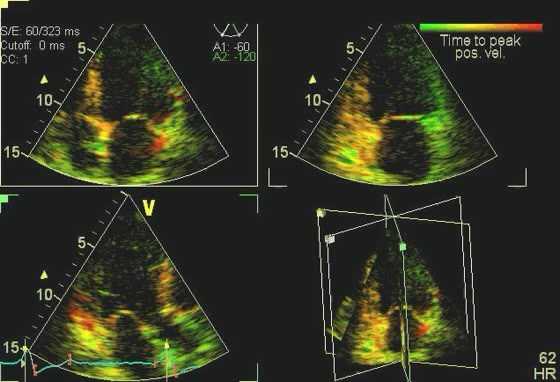

Спортсмены показывают нормальные или сверхнормальные показатели диастолической функции на ЭхоКГ, тогда как аномальное расслабление миокарда считается признаком ГКМП. Как и в случае со всеми другими аспектами этой болезни, паттерн наполнения миокарда колеблется от нормального у одних людей до серьезных нарушений у других. Различные параметры диастолической функции могут быть полезны для различения физиологической ГЛЖ и ГКМП, включая скорость притока ЛЖ, время замедления волны E, время изоволюметрической релаксации, тканевый допплер e ', соотношение E / e' и допплеровский кровоток в легочных венах. Спортсмены демонстрируют нормальные паттерны наполнения митрального клапана и нормальное соотношение E: A.

Используя тканевую допплерографию с импульсной волной для оценки скорости латерального кольца ЛЖ, спортсмены имеют нормальные или высокие значения e ', обычно значительно превышающие 10 см / с. Отношение E / e 'менее 8 также свидетельствует о нормальной физиологии сердечной мышцы. Измерения, проведенные рядом с медиальным кольцом митрального клапана, по-видимому, менее воспроизводимы при наблюдении за этим полезным эхокардиографическим открытием. Важно подчеркнуть, что, хотя все эти параметры полезны для диагностики ГКМП в крупных когортных исследованиях, их отсутствие достоверно не исключает ГКМП у спортсменов. Действительно, наш опыт показывает, что у большинства спортсменов (90%) с выявленной гипертрофической кардиомиопатией латеральное значение e '> 9 см / с, а у 92% - E / e'

У спортсменов на ЭхоКГ регистрируется нормальная систолическая функция, а у некоторых спортсменов на выносливость может наблюдаться погранично низкая фракция выброса из-за большой полости ЛЖ и брадикардии в покое. Напротив, люди с ГКМП имеют обычно высокую фракцию выброса и частичное сниженное укорочение, потому что у них обычно небольшая полость ЛЖ. Однако при оценке систолических кольцевых (S a) скоростей с помощью импульсно-волнового тканевого допплера большинство пациентов с ГКМП имеют низкие скорости ниже 10 см/с.

У спортсменов на эхокардиографии регистрируют гораздо более высокие значения, обычно значительно выше 10 см/с. Тканевые допплеровские исследования продольной деформации показывают, что спортсмены с физиологической ГЛЖ демонстрируют нормальные гомогенные паттерны деформации, тогда как пациенты с ГКМП имеют низкую и гетерогенную картину деформации. Исследование пациентов с ГКМП, спортсменов и здоровых людей из контрольной группы показало, что глобальная продольная деформация